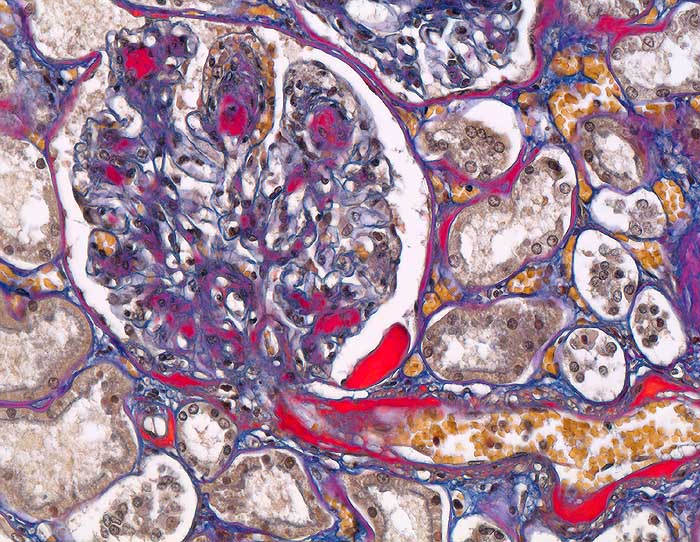

PathoPic – image database / PathoPic ID 6180 - Diabetische noduläre Glomerulosklerose Kimmelstiel-Wilson

Diabetische noduläre Glomerulosklerose Kimmelstiel-Wilson

Niere

Arteriolosklerose von Vas afferens und efferens. Noduläre Mesangiumverbreiterung. Kapseltropfen im Bowman'schen Kapselraum.

Diabetes mellitus Typ II seit 20 Jahren.

Histologie

200